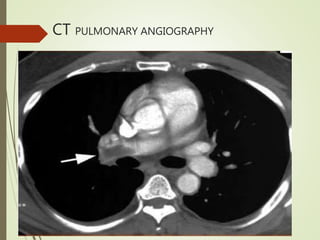

CT PULMONARY

ANGIOGRAPHY

 It is investigation of

choice

CT PULMONARY ANGIOGRAPHY